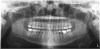

Panoramic

A digital panoramic radiograph (Figure 2) is indicated for circumstances in which intraoral imaging is not practical, as in patients who cannot open their mouth due to trismus or in those who cannot tolerate having a sensor or film in their mouth due to severe mucositis following radiation therapy for cancer. Advantages of panoramic imaging are that it quickly provides broad coverage of facial bones and teeth, it is convenient for both dental practitioner and patient, and is a helpful visual aid in patient education and case presentation.

Drawbacks of panoramic imaging are the cost—$25,000 to $85,00020 —and that vertical beam angulation is not adjustable. Also to keep in mind is that, like a traditional panoramic machine, the digital unit requires dedicated operatory space, so there is no space savings other than not needing a darkroom.

Figure 2. Panoramic radiographs are options when intraoral radiography is impractical or additional diagnostic information is required.

Figure 2